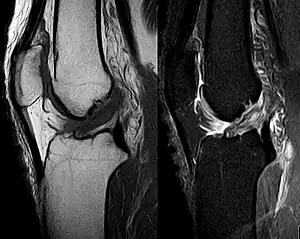

Anterior cruciate ligament tear seen on MRI. T1 left, right PDW.

Though clinical examination in experienced hands can be accurate, the diagnosis is usually confirmed by magnetic resonance imaging, which provides images of the soft tissues like ligaments and cartilage around the knee.[1] It may also permit visualization of other structures which may have been coincidentally involved, such as the menisci or collateral ligaments.[30] An x-ray may be performed in addition to evaluate whether one of the bones in the knee joint was broken during the injury.[9]

MRI is perhaps the most used technique for diagnosing the state of the ACL, but it is not always the most reliable technique as the ACL can be obscured by blood that fills the joint after an injury.[31]

MRI is particularly useful in cases of partial tear of the ACL. The anteromedial band is most commonly injured compared to the posterolateral band.[32]